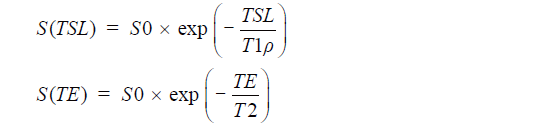

We used MINC tools and Display software (McConell Brain Imaging Center, Montreal, Quebec, Canada) to analyze the images. The relaxometry maps were generated using homemade scripts based on MINC tools from the corresponding data. T1ρ and T2 maps were computed on a pixel-by-pixel basis using an exponential decay model (Figure 1). S0 and S(TSL) are the equilibrium magnetisation signal and T1rho-prepared magnetisation signal with the spin-lock time of TSL. S(TE) is the signal acquired with the echo time (TE):